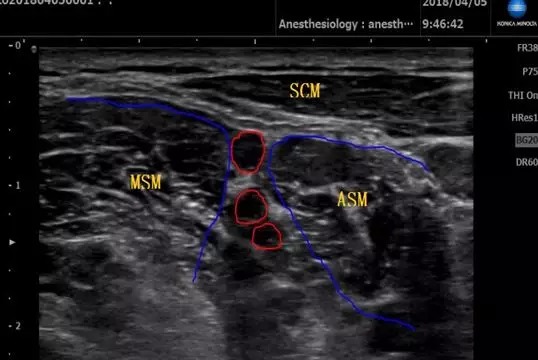

柯尼卡美能達攜明星產品SONIMAGE HS1助力Workshop環節,對肩、肘、腕、髖、膝、踝關節實際操作超聲檢查。

參會醫生學習熱情高漲,圍在帶教專家周圍,根據超聲屏幕上顯示的圖像,不斷發出提問,專家一一耐心講解。